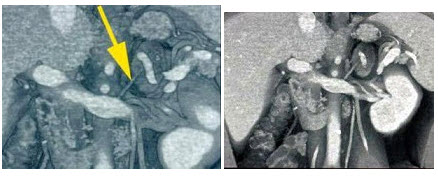

27、单项选择题

女性,50岁,腹痛,有肾细胞癌病史,结合所示图像,最可能的诊断是()

A.肾细胞癌转移

B.胰腺胰岛细胞瘤

C.胰腺腺癌

D.良性肿瘤

E.以上都不是

点击查看答案

本题答案:微信扫下方二维码即可打包下载完整带答案解析版《★放射医学(医学高级)》或《放射医学(医学高级):CT》题库

28、单项选择题